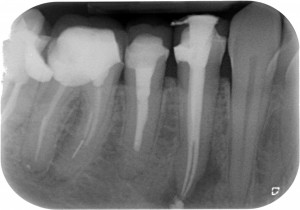

E arrivandomi il microscopio ho cominciato a trovare anatomie assurde a josa…E le riuscivo a chiudere solo coi thermafil…anche se in realtà evidentemente credevo solo di farlo, perché era impossibile. Guarda questo primo premolare inferiore che ho ritrattato un mesetto fa…forcazione a 5 mm dal fondo del dente…in pratica una IV classe di Weine…Secondo te con cosa l’ho chiuso? ?

Thermafil - Anatomia difficile iniziale Thermafil - Anatomia difficile lunghezze Thermafil - Anatomia difficile finale